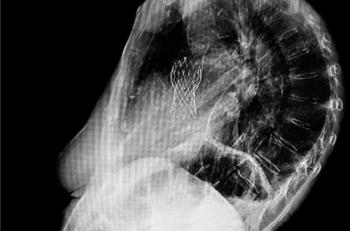

AHA Scientific Sessions 2019: Post-TAVR use of rivaroxaban is not recommended for routine use among patients with no indication for anticoagulation.